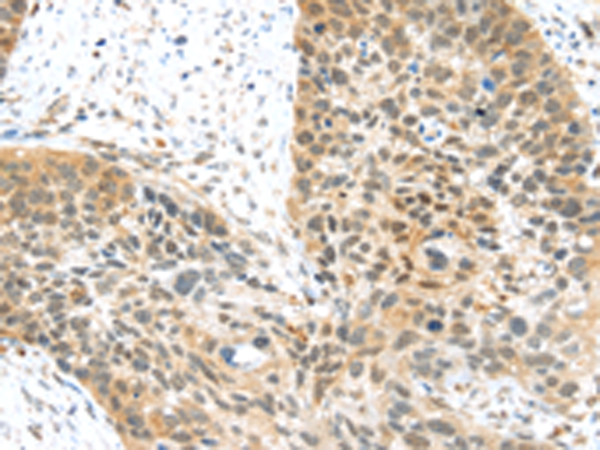

分类: 科研抗体货号: P11244别名: BAR; RNF47应用: IHC反应种属: Human